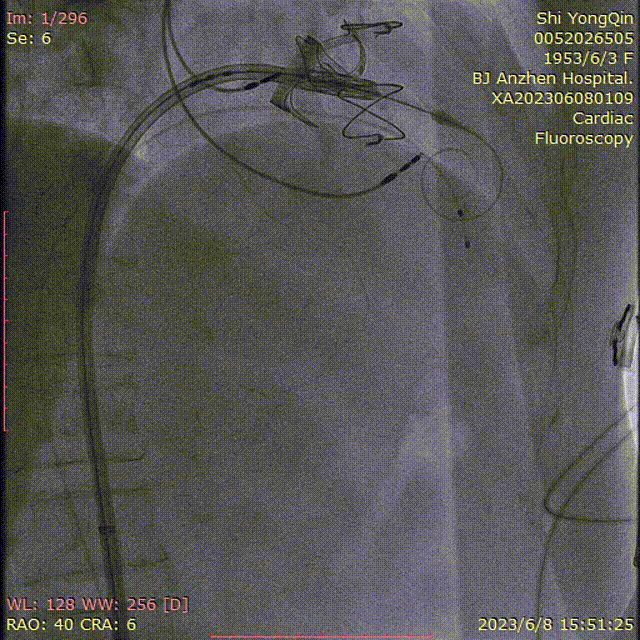

患者全麻,摆体位可寻找衰败生物瓣的切线投照体位,后消毒铺巾,穿刺双侧股静脉,左侧股静脉植入临时起搏器,右侧股静脉作为主入路,在超声指引下,按术前CT评估要求穿刺房间隔到达左心房,肝素化后(ACT>250秒),导入Agilis可调弯鞘管到达左心房,Pig造影导管跨过二尖瓣到达左心室心尖部,导入Safari导丝到达左心室;以12×40mm球囊扩张房间隔确认SAPIEN 3瓣膜可通过后,导入反向安装的23mm+3ml瓣膜到达下腔静脉,组装成功后,翻转其调弯系统后送入到左心房,跨过衰败的二尖瓣,在切线投照体位定位精确后,快速心室起搏下释放瓣膜,见瓣膜位置良好,超声显示无瓣周漏,测量左心室和桡动脉压差稍增高,超声显示LVOT流速稍增快;撤出瓣膜输送系统及导丝,撤出临时起搏电极,局部加压包扎,患者清醒后安返病房。

超声指引下房间隔穿刺

可调弯鞘指引下跨瓣

房间隔穿刺点扩张

球囊测试瓣膜的通过性